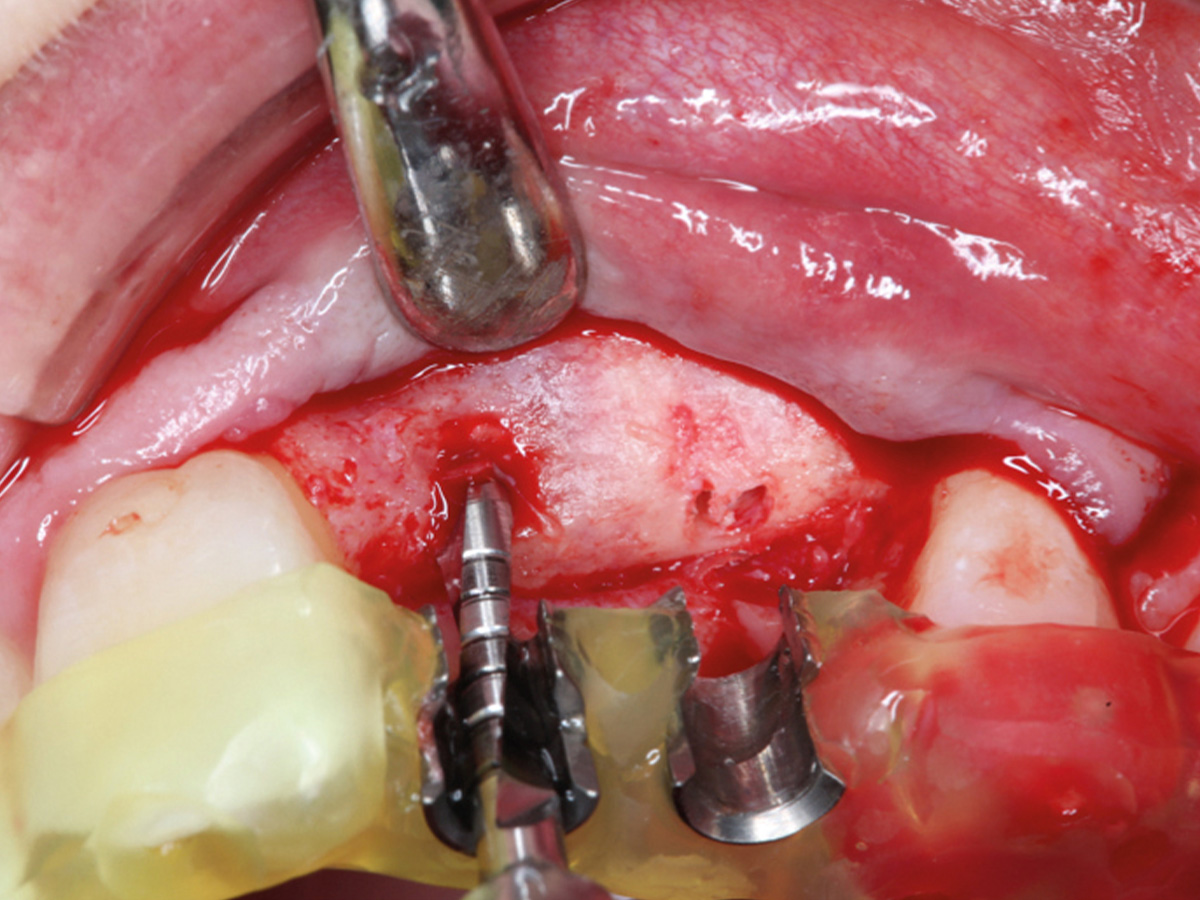

Abbildung 21

Implantation.

Abbildung 22

Darstellung der Implantat-Kavitäten im neuen Knochen.